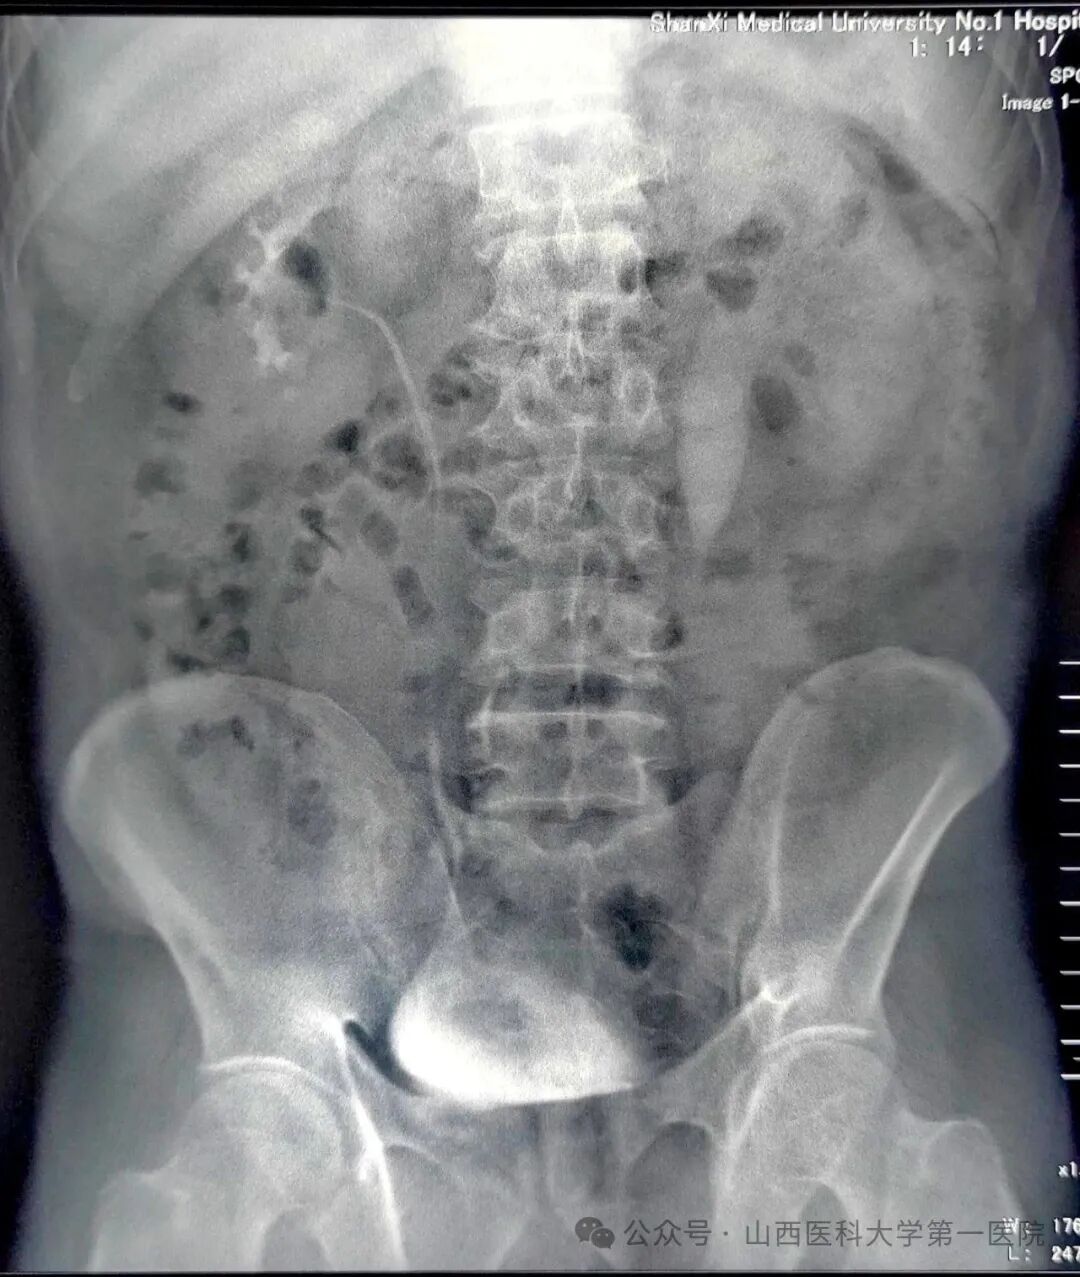

55岁男性患者,2024年3月因“左侧输尿管结石”在外院行输尿管镜碎石术;2024年9月在外院诊断为“左侧输尿管上段狭窄”,狭窄段长约3cm,行“开放左侧输尿管成形术”,术后半年拔除输尿管支架管,复查显示肾积水无改善;2025年4月,为求进一步诊治就诊于山医大一院,经影像学检查明确诊断为“左侧输尿管上段狭窄”,此次狭窄段长约1cm,位于既往手术区域。

术前IVP